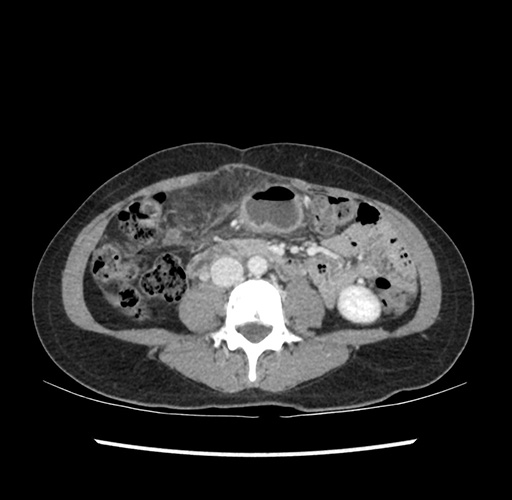

Imaging Analysis

Look through the patient's CT scan to identify any areas of concern for the necessary procedure.

Based on your CT findings, which issue(s) would give reason for "planned slowing down moment(s)" in this case?